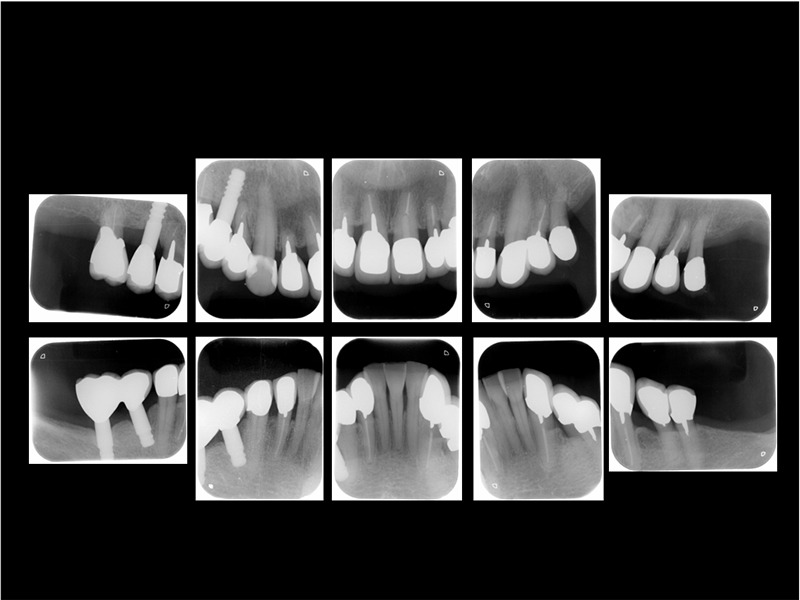

治療前X線写真